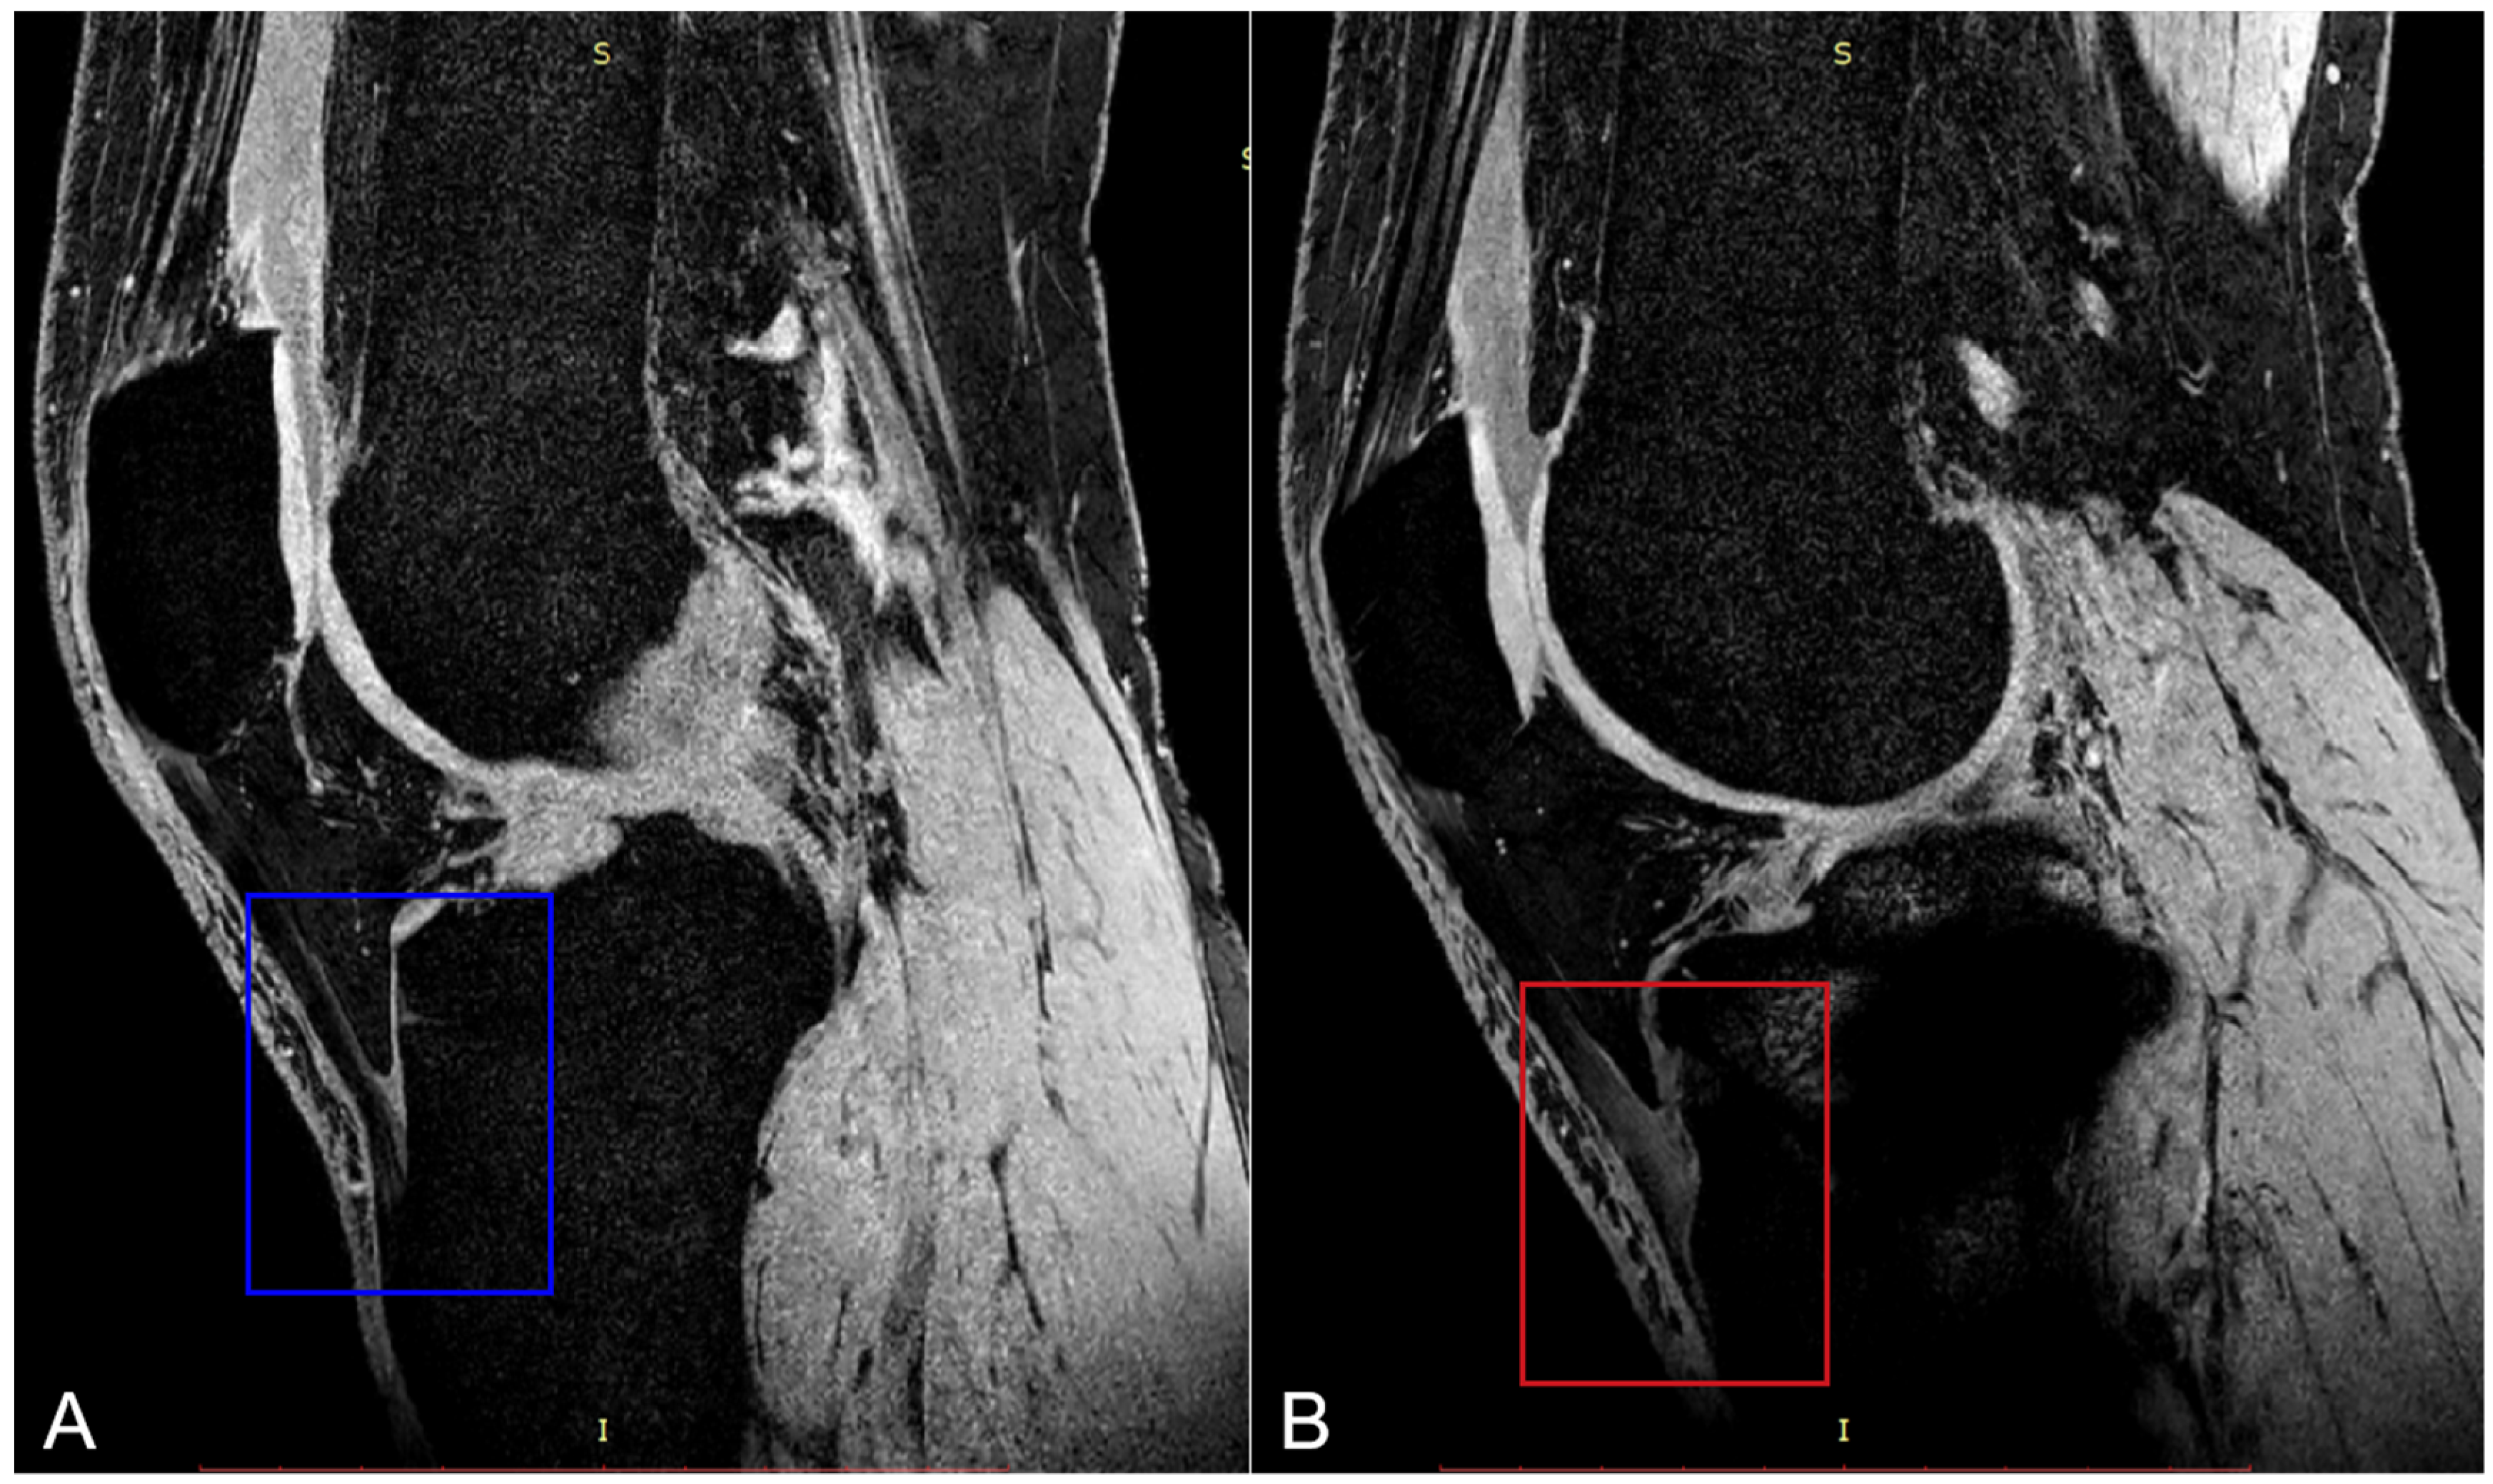

2. Materials and Methods